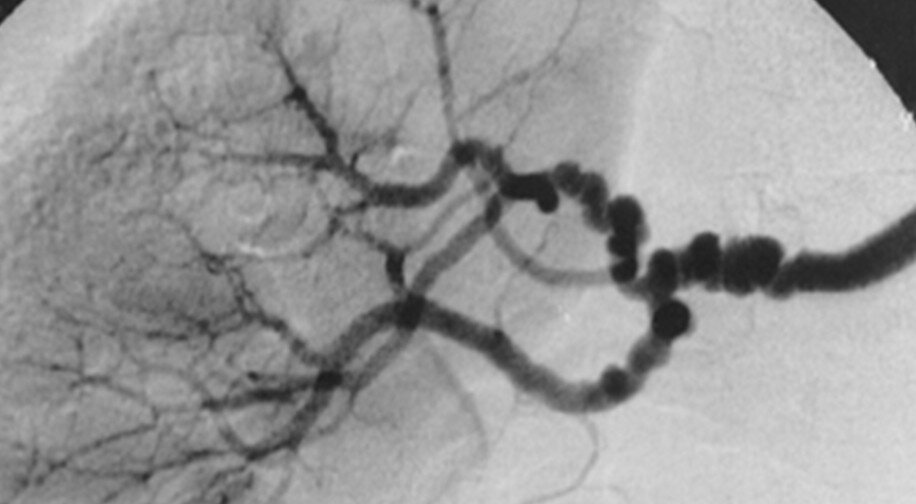

показан классический симптом «нитка бус» при фибромышечной дисплазии